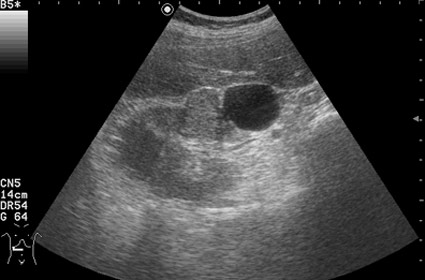

Изменения правой почки у мужчины 56 лет - кисты и RCC

Профилактический осмотр.

Как трактовать выявленные изменения? Какова тактика врача УЗД в данной ситуации?

Вас не смущает наличие внутреннего кровотока в одной из "кист"?

Дольчатость почки в 56 лет?Uzgraph писал(а):А разве это киста?

Обозначенный сегмент почки по структуре не отличим от рядом лежащих участков, выбухание контура над указанным сегментом тоже ни о чем не говорит, т.к. может быть просто дольчатостью.

При гистологии эта структура была почечно-клеточным раком (RCC).

Согласен, но есть совокупность признаков, позволяющих с очень высокой степенью достоверности считать, что это тканевое образование, а в отношении конкретного случая - что это почечноклеточный рак (RCC).Uzgraph писал(а):УЗИ не метод гистологической верификации - по УЗИ рак не ставят.

В данном конкретном случае разница есть и она довольно существенная. Все-таки образование представленное на этой странице изо- или нормоэхогенное. В Вашем случае образование имеет повышенную эхогенность, примерно равную эхогенности окружающей почку клетчатки, что в пользу именно AML.

Но Вы правы в том, что могут быть трудности в дифференциальном диагнозе между AML и RCC малых размеров (в 20-30 % случаев могут быть эхогенными). Однако при УЗИ для RCC характерен гипоэхогенный ободок, внутриопухолевые включения, низкорезистивный внутриопухолевый кровоток.